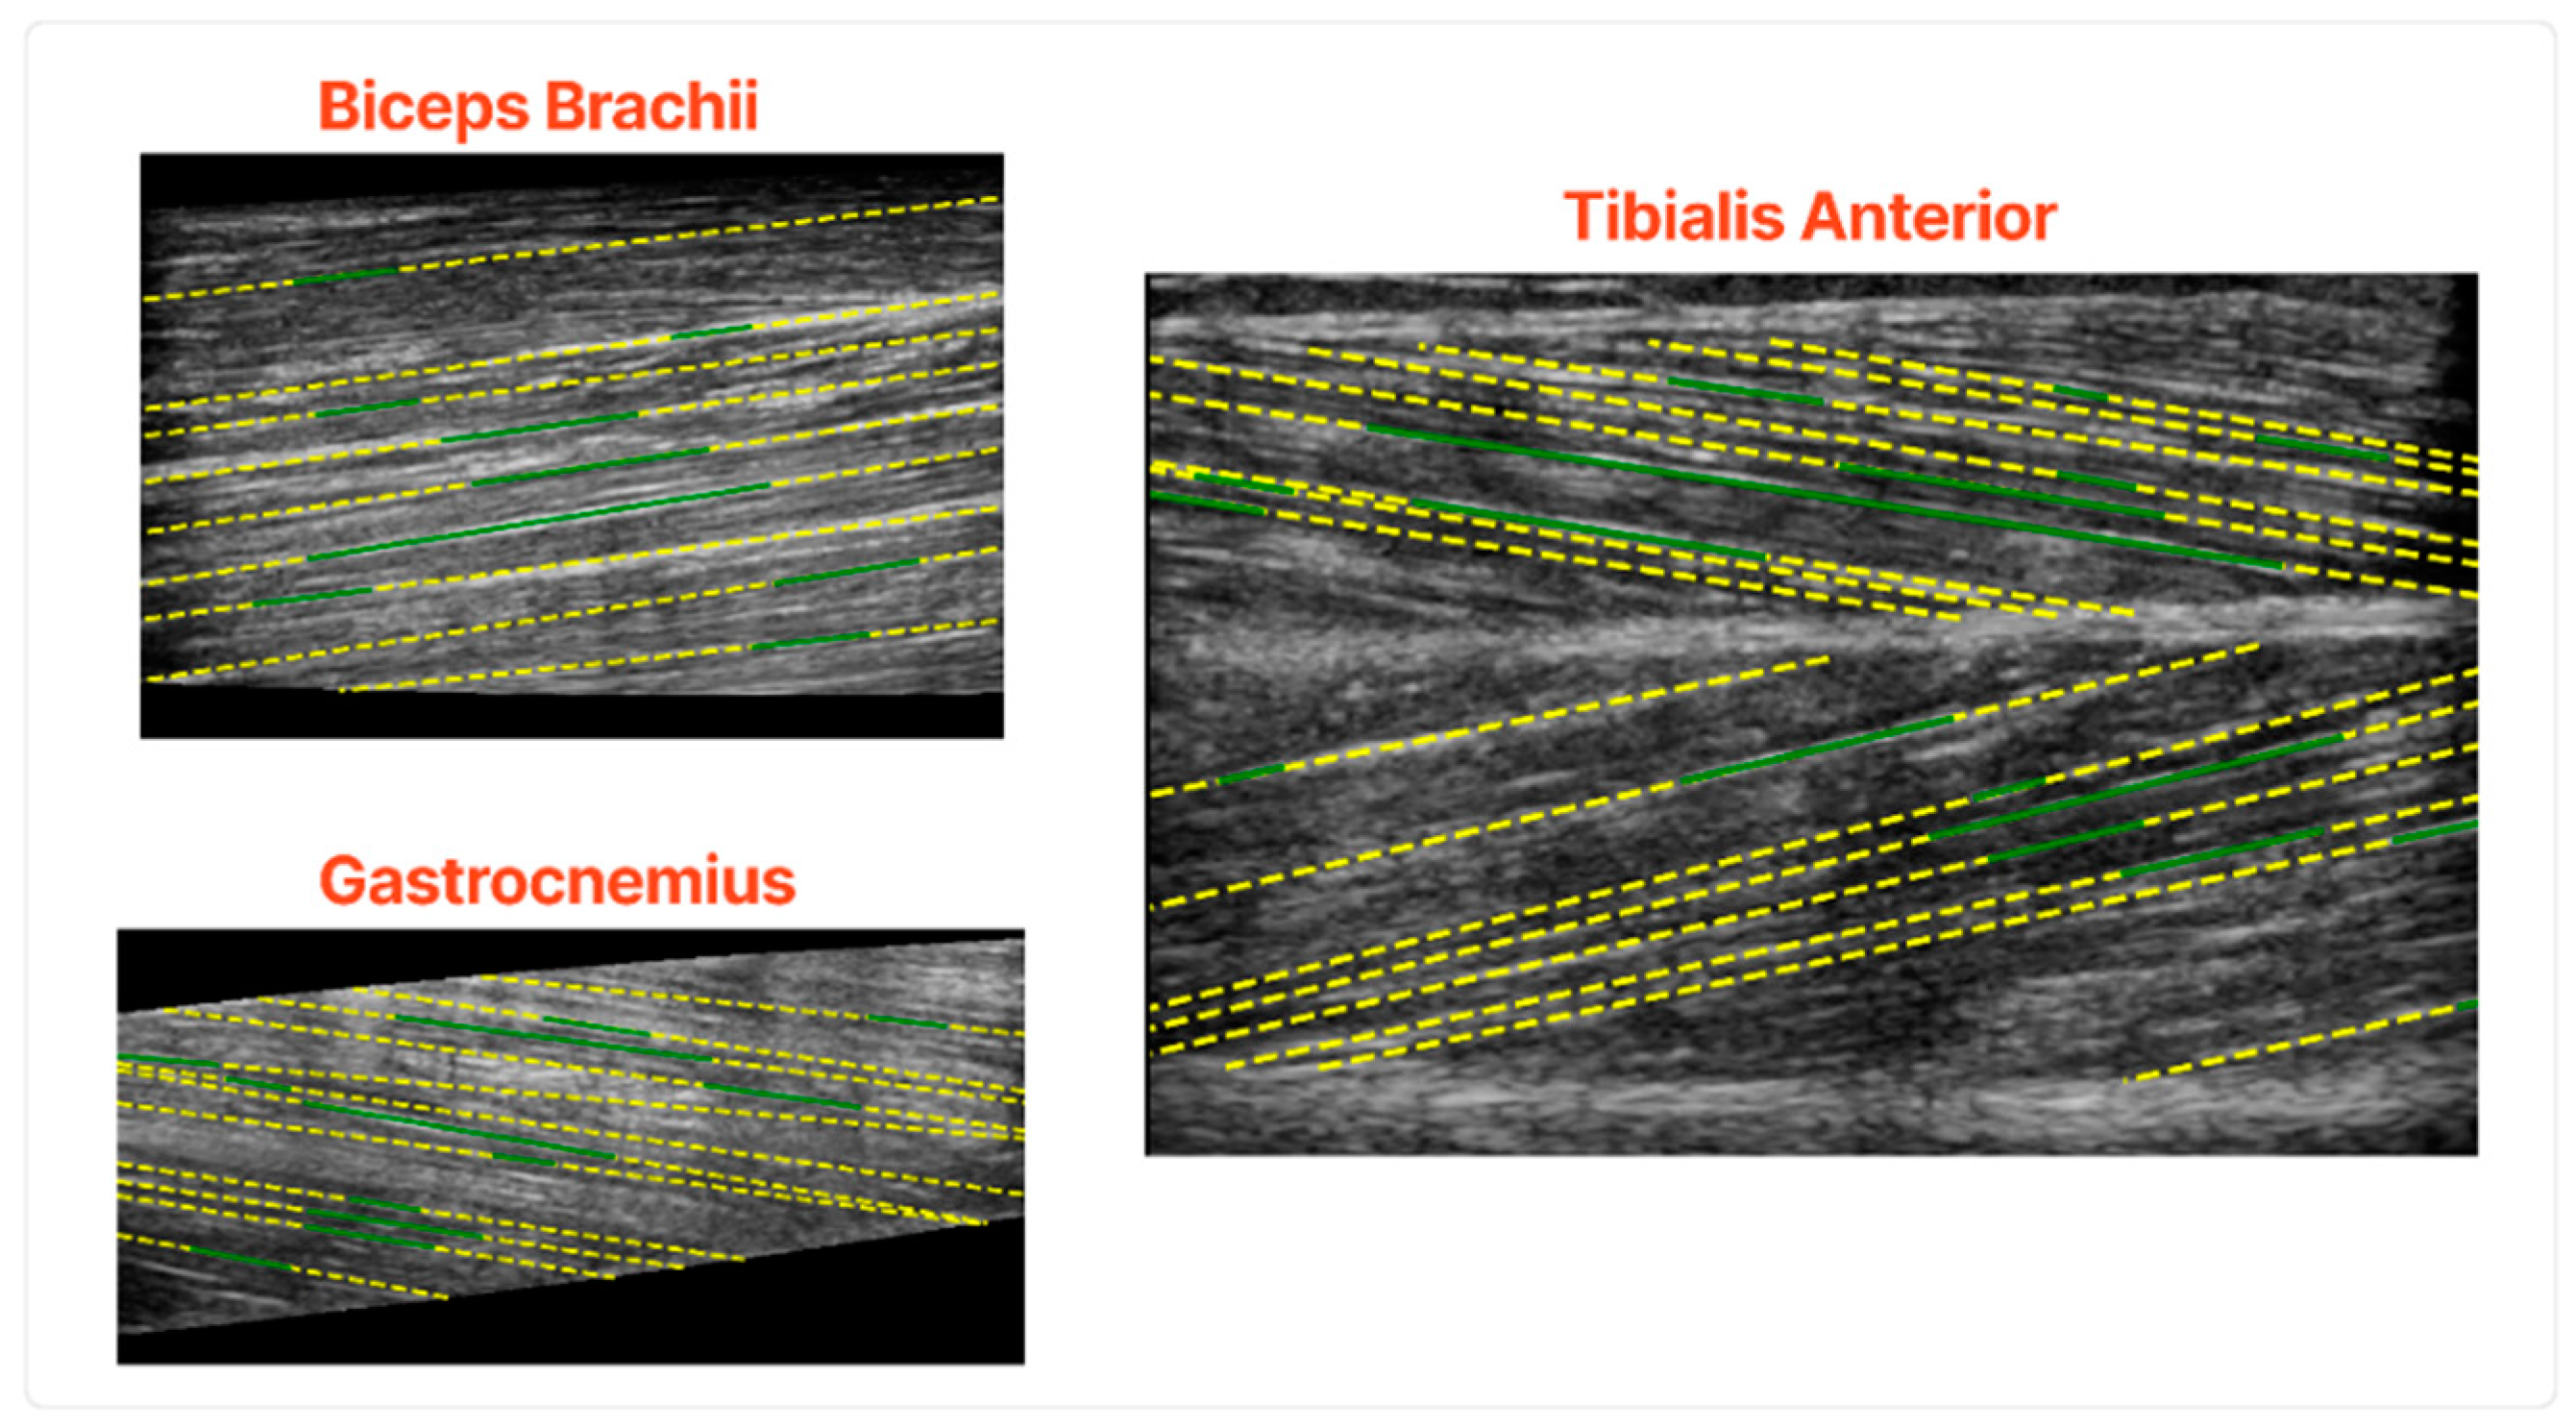

In Figure 8, some characteristic results of the fascicles extraction algorithm are depicted. The results show that the proposed pipeline can accurately extract the main fascicles in all the examined muscle sections. Another advantage of the proposed algorithm is that it works in an unsupervised fashion since it does not need exhaustive annotation of the fascicles, a tedious and time-consuming task.

Figure 8. Qualitative results of the fascicles extraction in the validation set. The green lines are the algorithm’s output before the fascicles extended in the whole muscle and the yellow lines after.

The fascicles with the highest intensity gradients are the ones which are detected consistently. On the other hand, fascicles of low contrast and not well defined were the ones that the algorithm struggled to delineate. Moreover, the early steps of the algorithm would detect fascicles in multiple small segments, a problem that is tackled in the subsequent steps of the fascicle detection process.